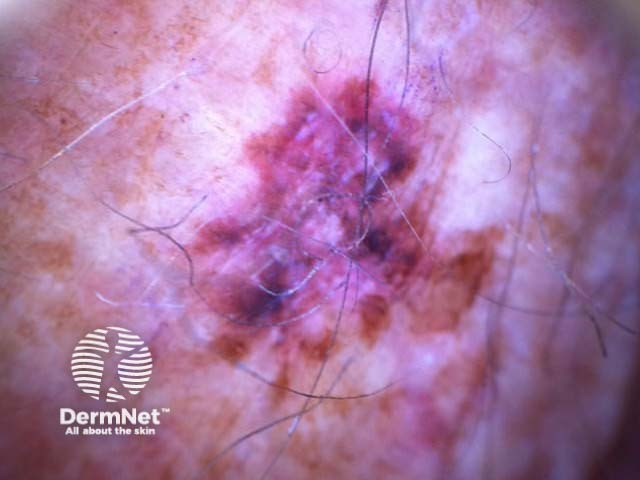

C=4, A=1, S=1, H=4. Total CASH score=10 C=4, A=2, S=2, H=5. Total CASH score=13 C=4, A=1, S=1, H=3. Total CASH score=9 C=3, A=1, S=2, H=3. Total CASH score=9 C=4, A=2, S=2, H=3. Total CASH score=11 C=4, A=2, S=2, H=4. Total CASH score=12